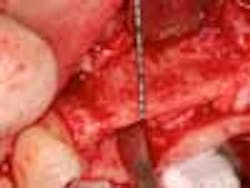

Fig. 7